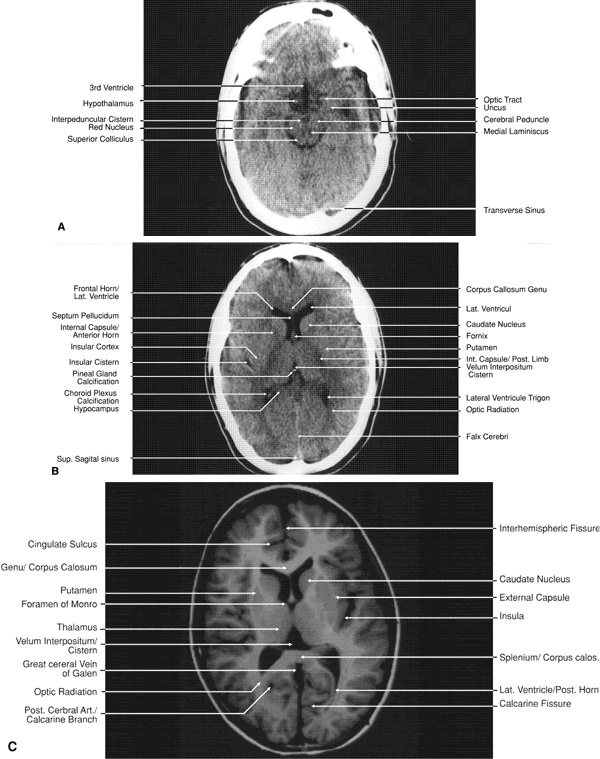

The globe is shown in Figure 12. The orbit and periorbital structures are shown in Figures 13 through 16, and the optic canal is shown in Figures 17 through 26. The cavernous sinus and optic chiasm are shown in Figures 27 and 28, and the posterior visual pathway and cranial nerves are shown in Figures 29 through 33.

Fig. 32. A. Axial computed tomography soft tissue image at the level of suprasellar cistern. B. Axial computed tomography soft tissue image at the level of thalamus. C. Axial T1-weighted image at the level of thalamus.